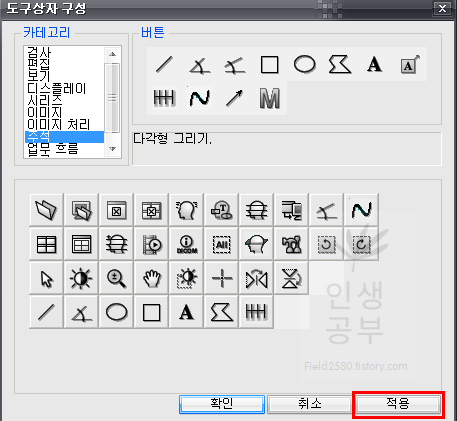

카테코리에 있는 모든 버튼을 보시는 것을 추천합니다. 위에 설명해드린 것은 제가 환자들과 함께 X-ray보면서 많이 사하는 것들이니 사용자에 따라서 선호하는 것들이 다를 수 있으니 한번 모두 다 보시고 추가할 것들은 추가하고 제거할 것들은 제거해주시는 것이 좋습니다. 카테고리에 있는 메뉴를 누르면 해당 메뉴에 버튼이 나오게됩니다. 이 버튼에 마우스를 가져대면 아래에 짧은 설명이 나오니 참고해주시기바랍니다. 어짜피 시간이 지나면서 잘 안쓰는 것들은 삭제하게 되니 필요에 따라서 삭제할 수도 있고, 필요한 것들은 다시 추가할 수 있으니 너무 많이 고민하지 않으셔도 됩니다. 본인에 맞게 메뉴가 세팅이 되었으면 적용버튼을 눌러줍니다.

왼쪽 상단에 본인이 설정한 도구상자로 바뀌었는지 확인해주시면 됩니다.

본인에게 맞는 도구상자가 구성 되었으면 적용버튼을 눌러줍니다.

적용버튼을 누르시면 왼쪽 상단에 본인에 맞게 변경된 도구상자를 확인할 수 있습니다.